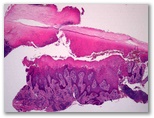

Granuloma piogenico

lesión tras crioterapia